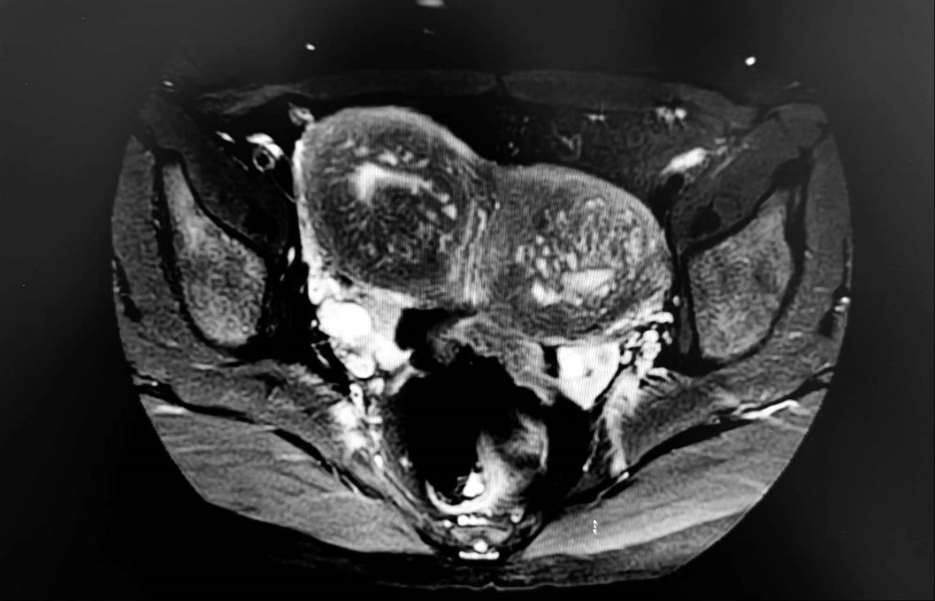

盆腔MRI:

1.子宫双宫颈、双子宫畸形。

2.子宫肌腺症并腺肌瘤改变。

3.右侧疤痕子宫。